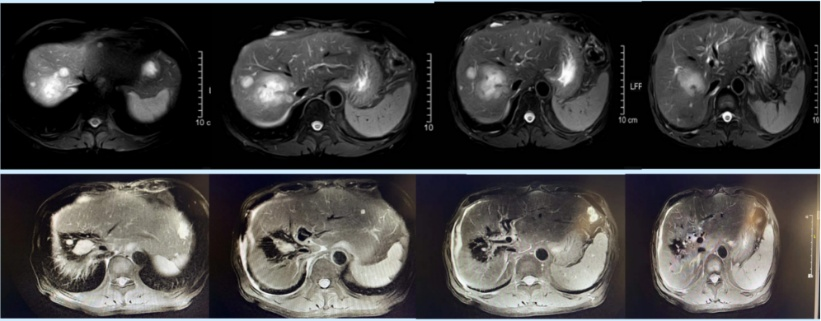

治疗初期,影像学检查显示病灶强化明显减退,肿瘤体积显著缩小,肿瘤标志物CA199亦明显下降,快速达到部分缓解(PR)状态。

△治疗前后影像(MRI)对比:2020年11月10日MRI(上)vs.2021年11月16日MRI(下)